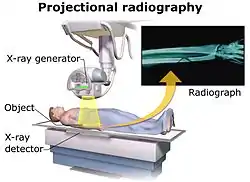

To obtain an image with any type of image detector the part of the patient to be X-rayed is placed between the X-ray source and the image receptor to produce a shadow of the internal structure of that particular part of the body. X-rays are partially blocked ("attenuated") by dense tissues such as bone, and pass more easily through soft tissues. Areas where the X-rays strike darken when developed, causing bones to appear lighter than the surrounding soft tissue.